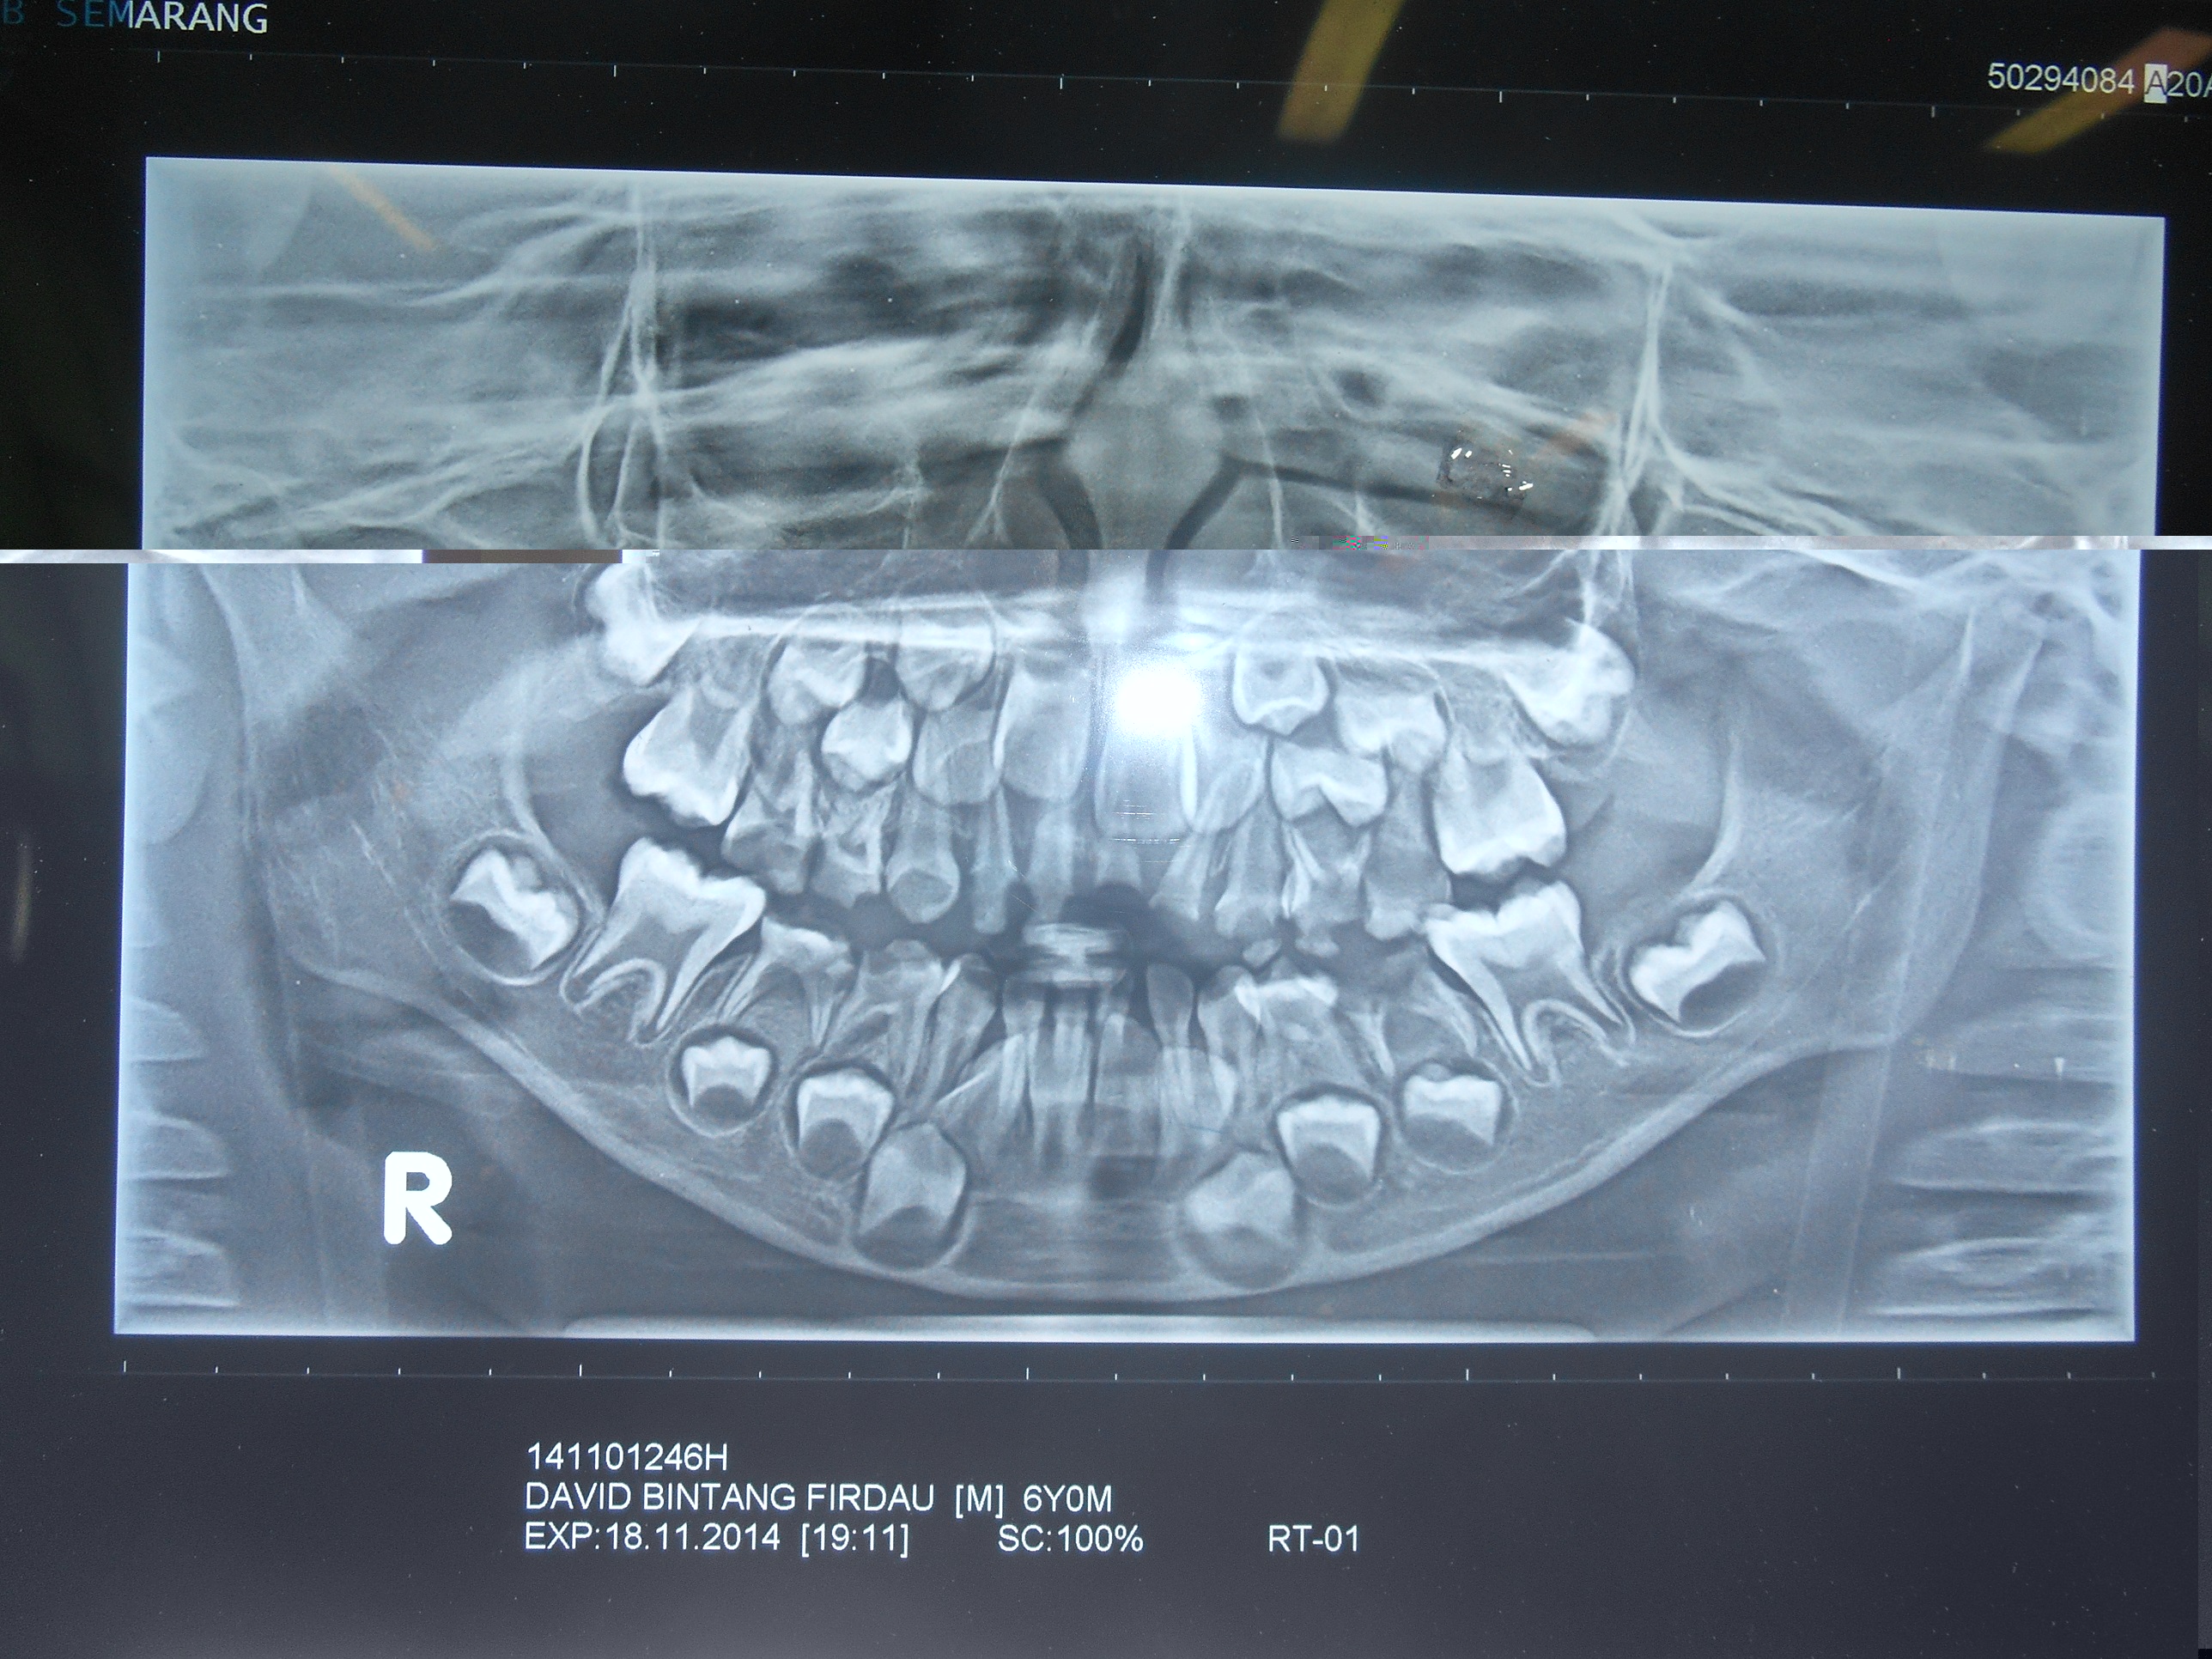

Perforasi iatrogenik merupakan salah satu resiko yang sering terjadi dalam perawatan endodontik yang disebabkan oleh kesalahan operator. Perforasi dapat terjadi pada apeks, lateral atau korona. Perawatan untuk perforasi dapat dilakukan dengan bedah atau non bedah. Prognosis dari perforasi endodonti dipengaruhi oleh beberapa faktor antara lain adalah waktu terjadinya perforasi, lokasi perforasi dan besarnya perforasi. Tujuan laporan kasus ini untuk melaporkan perawatan perforasi korona pada pulpektomi gigi decidui. Kasus seorang anak laki-laki usia 6 tahun datang bersama ibunya dengan keluhan gigi bawah belakang kanan sering sakit tiba-tiba sejak tiga bulan yang lalu. Diagnosis pada gigi molar pertama kanan rahang bawah adalah karies profunda kelas I dengan pulpitis irreversible. Perawatan yang dilakukan adalah pulpektomi. Dalam proses perawatan terjadi perforasi korona di mesial yang disebabkan oleh trauma bur preparasi saat dilakukan pembukaan atap pulpa. Perawatan pulpektomi tetap dilanjutkan dengan menutup daerah perforasi dengan zinc phosphat cement dan diakhiri dengan tumpatan tetap stainless steel crown (SSC). Kesimpulan dari laporan kasus ini yaitu perawatan perforasi korona dengan non bedah pada pulpektomi gigi decidui mempunyai prognosis yang baik. Perawatan dilakukan dengan bahan tumpatan yang memiliki ketahanan terhadap saliva dan tidak mengiritasi pulpa ataupun gingiva.